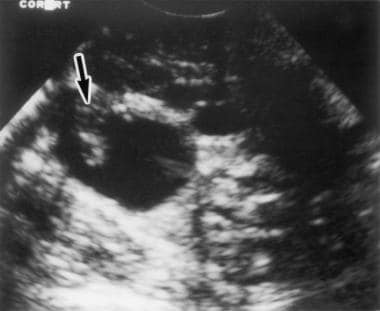

난소암은 초기증상이 거의 없기 때문에 환자의 절반 이상이 전이가 일어난 상태에서 의료기관에 방문하여 암을 진단받게 되며, 암이 어느 정도 전이했는지에 따라 난소암의 생존율이 달라지게 됩니다.

난소암은 초기에는 증상이 거의 없어 조기 발견이 어렵고, 진단이 늦어지면 치료가 어려워지는 경우가 많습니다. 따라서 여성들은 난소암의 초기 증상과 원인에 대해 잘 알고, 정기적인 건강검진을 받는 것이 중요합니다.

난소암은 초기에는 증상이 거의 없어 조기 발견이 어렵습니다. 하지만 난소암이 진행되면 다음과 같은 난소암 초기증상이 나타날 수 있습니다.